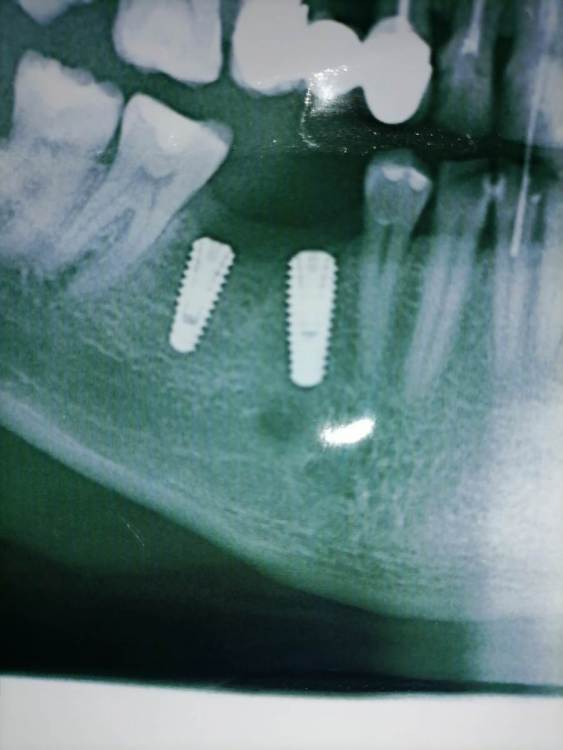

Sergey5263883 Опубликовано 23 января, 2022 Поделиться Опубликовано 23 января, 2022 (изменено) Добрый день! Уважаемые доктора подскажите пожалуйста, 2,5 месяца назад поставили импланты megagen . Спустя 2 месяца поставили формирователи. За все это время никаких болей, жалоб и тд у меня не было. Вчера случайно обратил внимание, что формирователь на 6-ке с одной стороны как бы оголен, или не утоплен. Скажите пожалуйста это нормально? Очень переживаю Снимок к сожалению есть только до установки Формирователя Изменено 23 января, 2022 пользователем Sergey5263883 Ссылка на комментарий